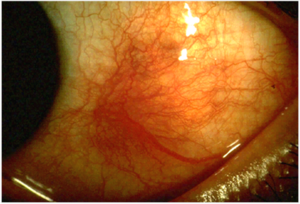

التهاب الصلبة (إنگليزية: Scleritis)، هو is a serious inflammatory disease that affects the white outer coating of the eye, known as the sclera. The disease is often contracted through association with other diseases of the body, such as granulomatosis with polyangiitis or rheumatoid arthritis. There are three types of scleritis: diffuse scleritis (the most common), nodular scleritis, and necrotizing scleritis (the most severe). Scleritis may be the first symptom of onset of connective tissue disease.[1]

The pain of episcleritis is less severe than in scleritis.[4] In hyperemia, there is a visible increase in the blood flow to the sclera (hyperaemia), which accounts for the redness of the eye. Unlike in conjunctivitis, this redness will not move with gentle pressure to the conjunctiva.